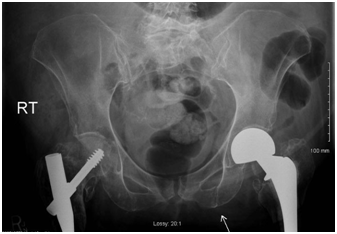

Our patient presented with left sided rib pain secondary to a mechanical fall. She also complained of pain on movement of both lower extremities. On initial presentation she was a wake, alert and oriented with stable vital signs. Initial examination revealed left leg superficial bruises and a decreased range of motion of both lower extremities. The rest of the physical examination was unremarkable. Radiographic imaging revealed left seventh rib fracture and a minimally displaced fracture of the left inferior pubicramus (Figure 1). Shortly after admission, she acutely developed lethargy, altered mental status, hypotension with blood pressure of 80/50mmHg and tachycardia with heart rate of 110 beats per minute. Pulseoximetry showed 82% oxygen saturation on four liters of oxygen via nasal cannula. The patient was transferred to the intensive care unit for close monitoring. There was transient clinical improvement with administration of bi-level positive airway pressure and fluid resuscitation.

Figure 1 Left inferior pubic ramus fracture, non­displaced, from a mechanical fall.